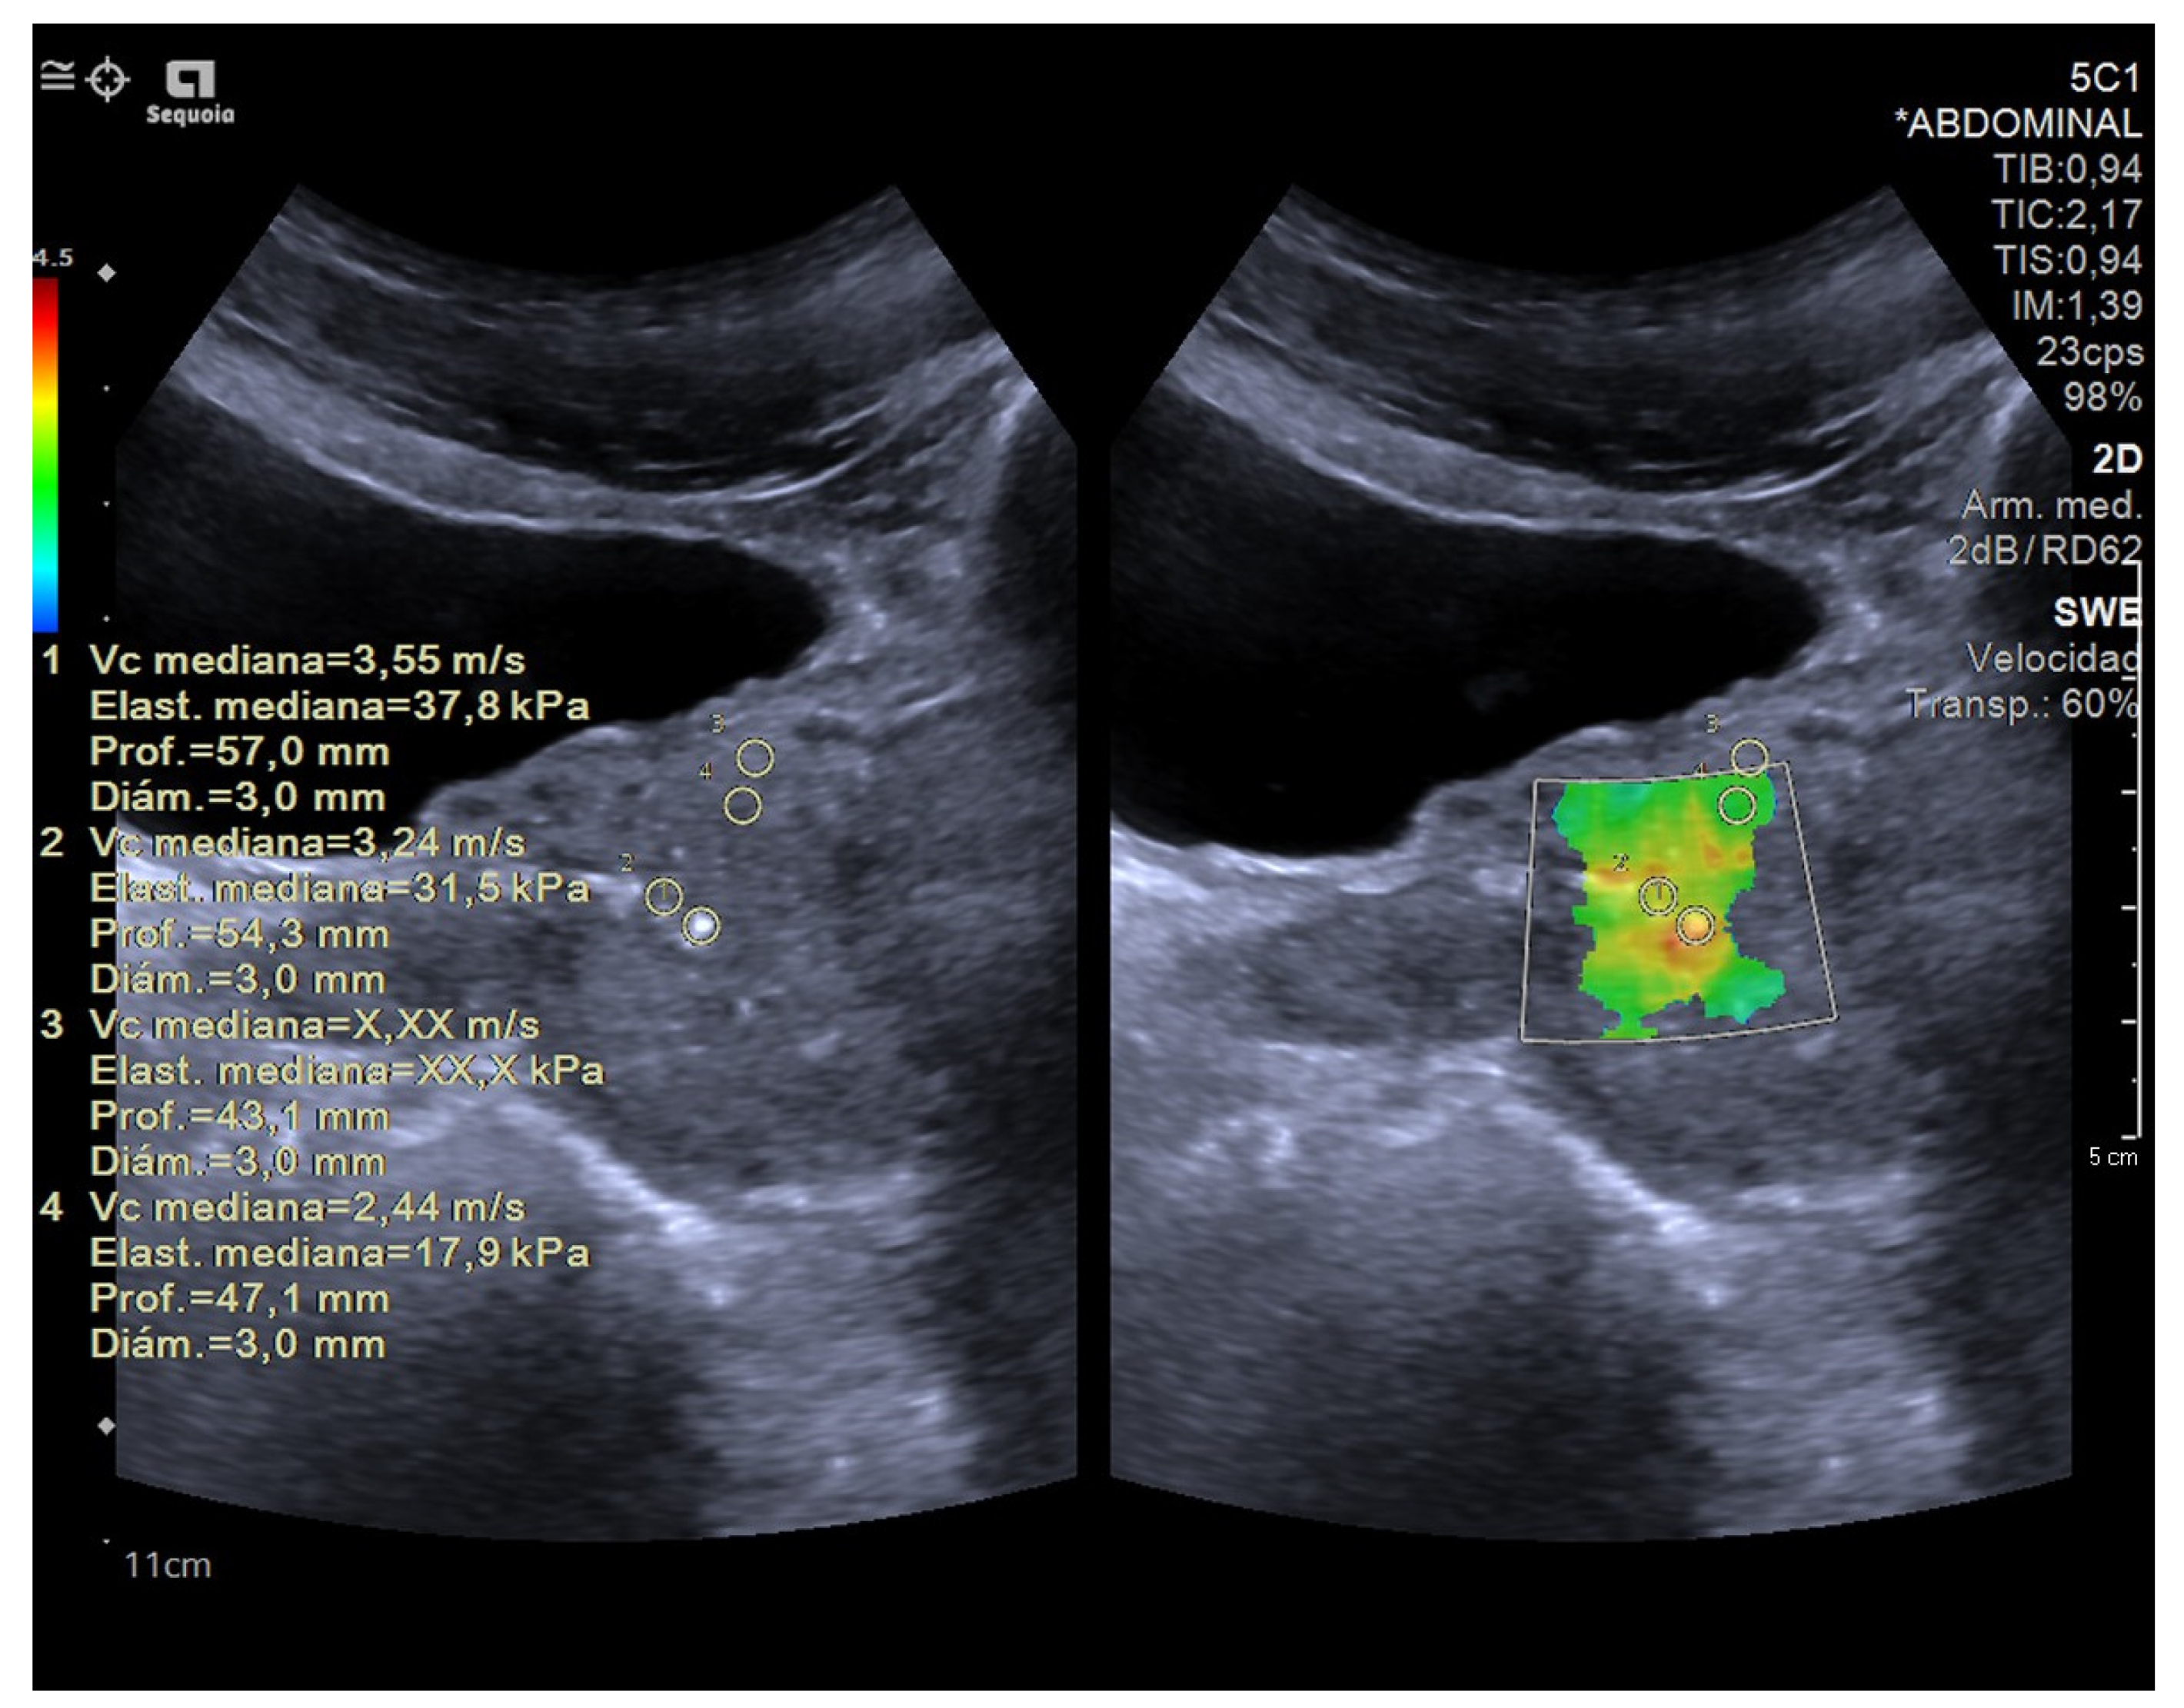

4.3. Elastography in Testicular Lesions

- Pedersen, M.R.; Moller, H.; Osther, P.J.S.; Vedsted, P.; Holst, R.; Rafaelsen, S.R. Comparison of Tissue Stiffness Using Shear Wave Elastography in Men with Normal Testicular Tissue, Testicular Microlithiasis and Testicular Cancer. Ultrasound Int. Open 2017, 3, E150–E155. [Google Scholar] [CrossRef]

- Rocher, L.; Criton, A.; Gennisson, J.L.; Creze, M.; Albiges, L.; Ferlicot, S.; Bellin, M.-F.; Izard, V.; Correas, J.-M. Characterization of Testicular Masses in Adults: Performance of Combined Quantitative Shear Wave Elastography and Conventional Ultrasound. Ultrasound Med. Biol. 2019, 45, 720–731. [Google Scholar] [CrossRef]

- Roy, C.; de Marini, P.; Labani, A.; Leyendecker, P.; Ohana, M. Shear-wave elastography of the testicle: Potential role of the stiffness value in various common testicular diseases. Clin. Radiol. 2020, 75, 560.e9–560.e17. [Google Scholar] [CrossRef] [PubMed]